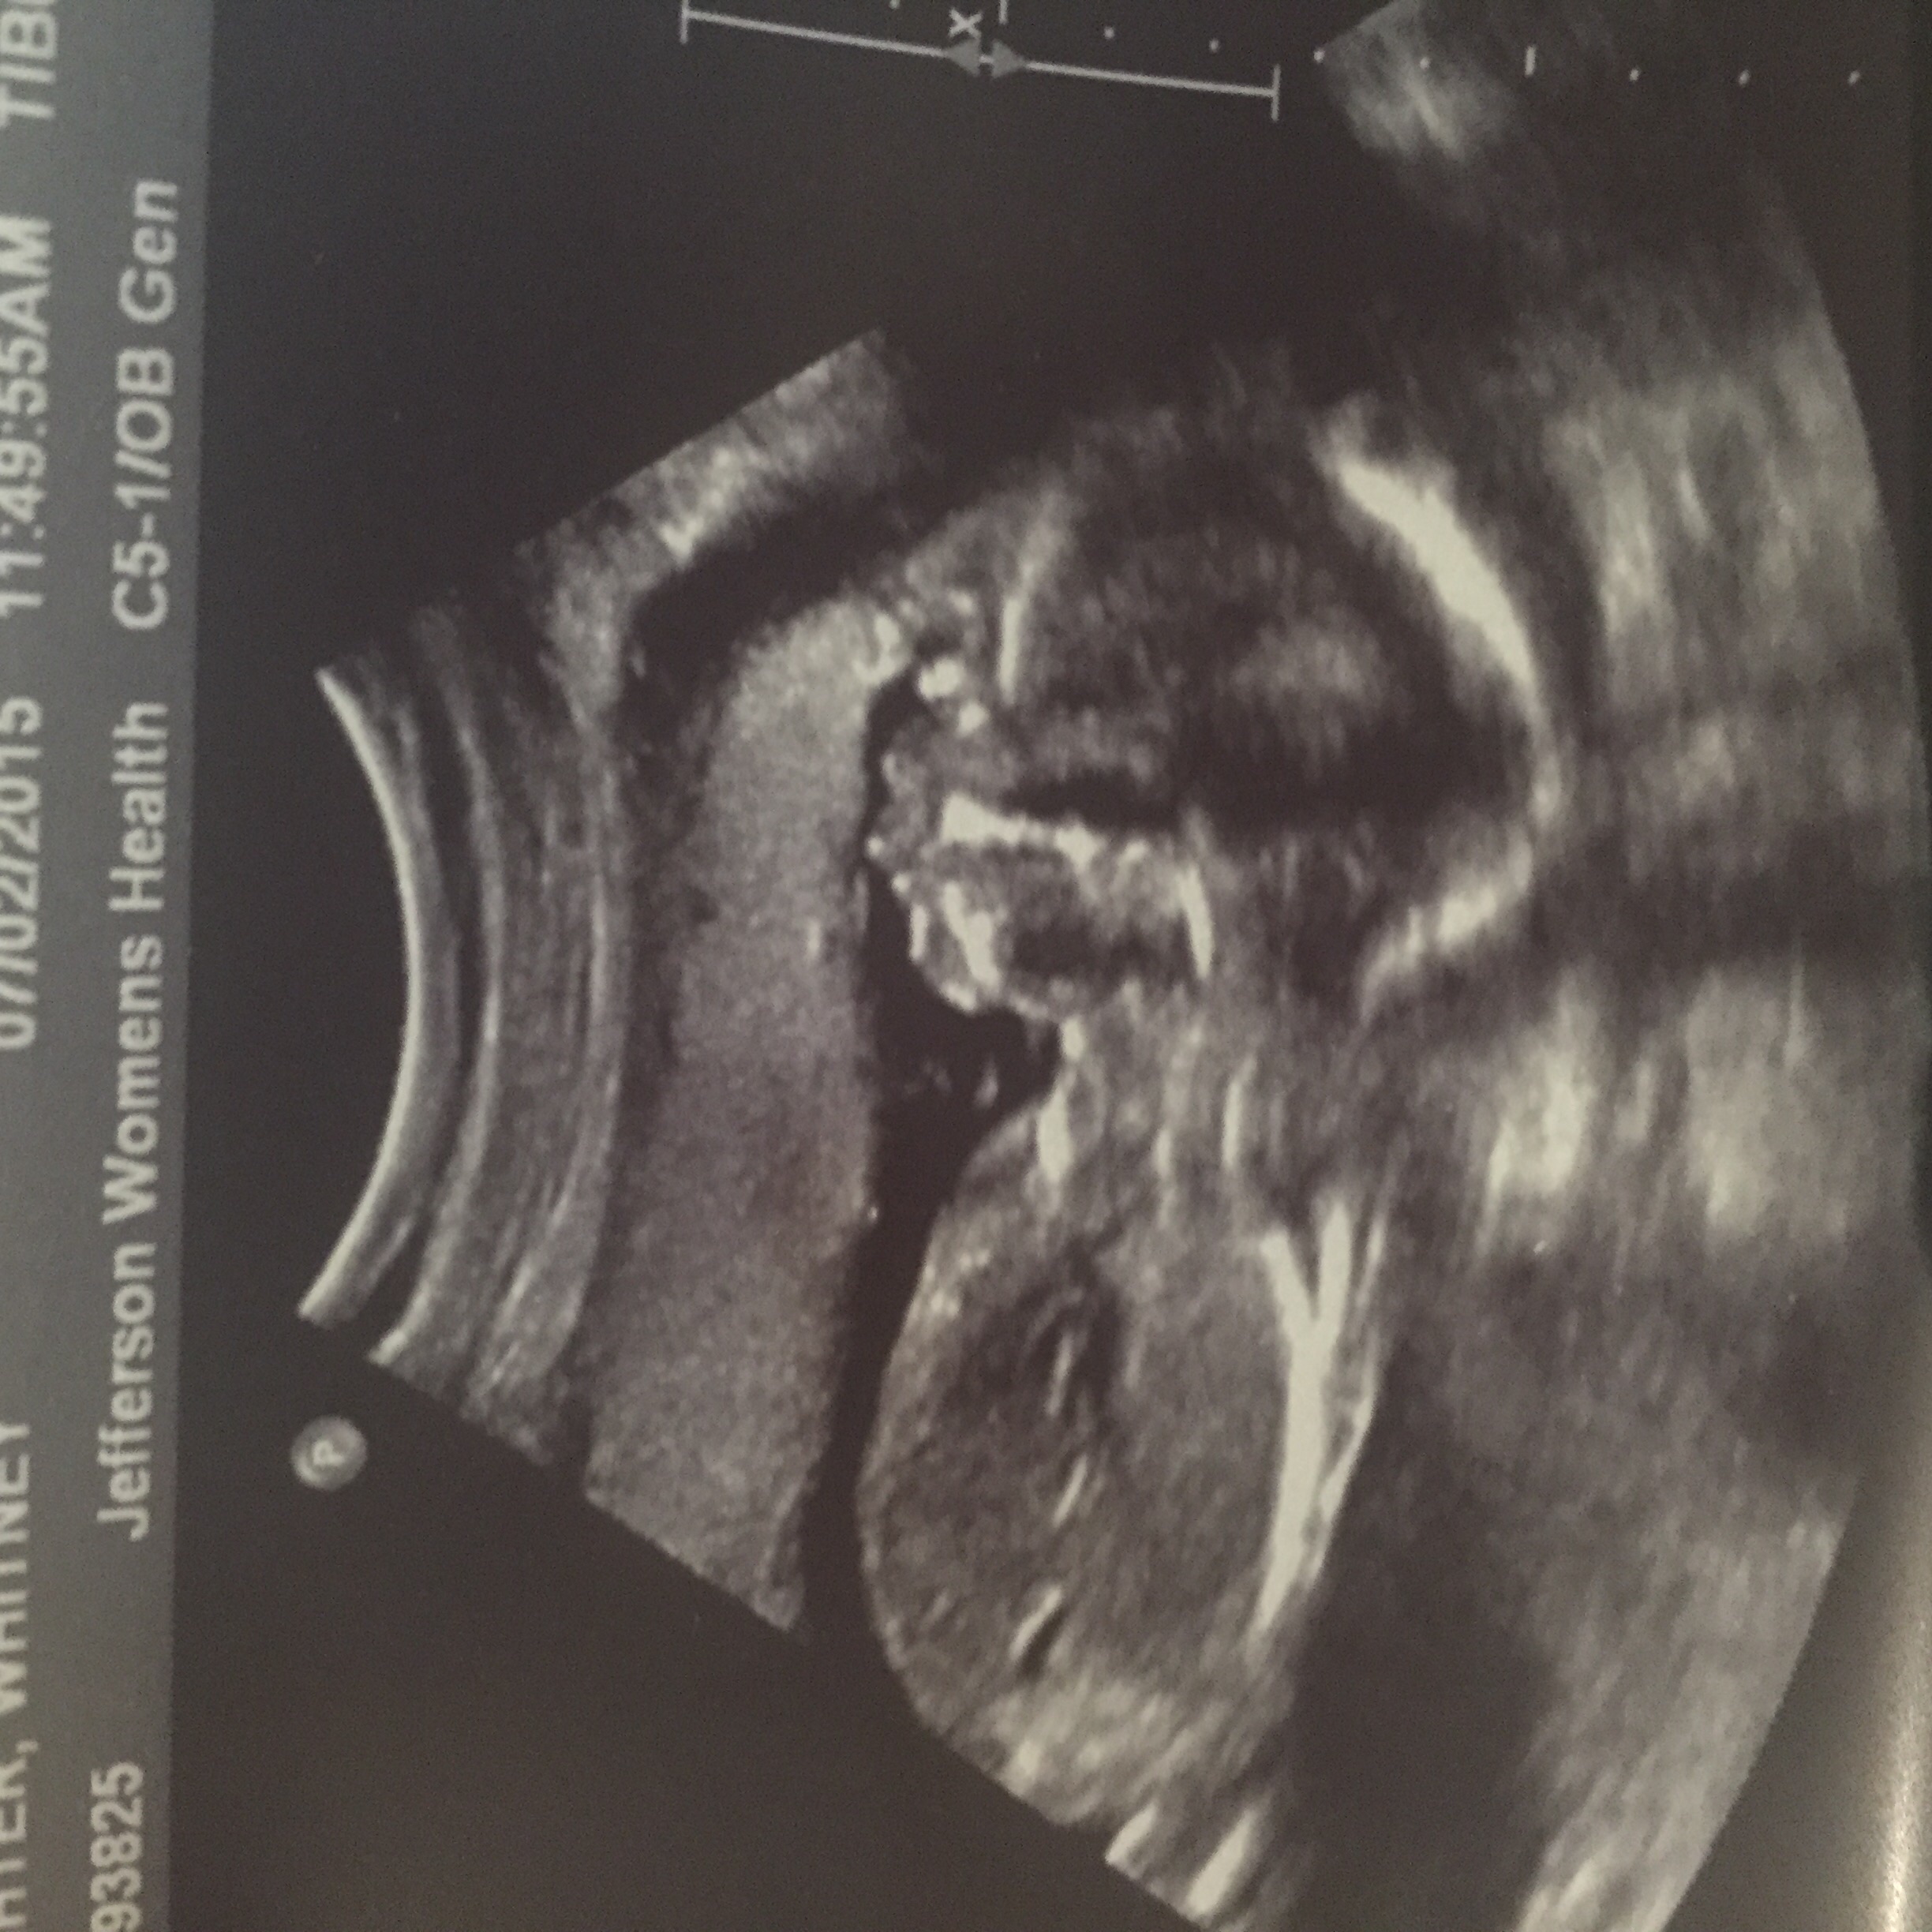

During the 20 week ultrasound anatomy scan, a trained technician or sonographer will use a handheld device (called a transducer) to send sound waves into your uterus. Most of the time, parents leave the 20-week scan with big smiles, having seen their baby in more detail than ever before

20 Week Scan Couldn't Measure Heart Is It OKay? Common Findings at the 20-Week Scan Typical Positive Outcomes I work in maternal fetal medicine so a lot of high risk patients come to us The 20-week scan, also known as the mid-pregnancy or anomaly scan, is a crucial ultrasound examination usually performed between 18 and 22 weeks of pregnancy

Source: vimasumaehj.pages.dev How Common Is Bad News At 20 Week Scan All You Need To Know Ada Jennifer , The 20-week scan plays a crucial role in assessing fetal development and identifying potential health conditions This scan provides detailed imagery of the baby, allowing doctors to observe growth patterns, check for structural abnormalities, and assess the development of organs and limbs.

Source: gblingheb.pages.dev 20 Week Scan...It's A...... Emmy's Mummy , The 20-week scan plays a crucial role in assessing fetal development and identifying potential health conditions It's common to get confirmation of the baby's sex and to see the tiny details of their face, hands, and feet